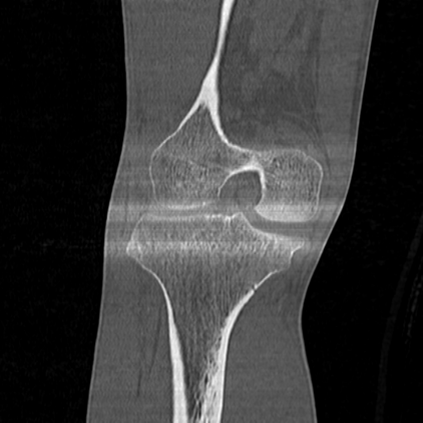

CT reconstruction provides radiologists with images for diagnosis and treatment, yet current deep learning methods are typically limited to specific anatomies and datasets, hindering generalization ability to unseen anatomies and lesions. To address this, we introduce the Multi-Organ medical image REconstruction (MORE) dataset, comprising CT scans across 9 diverse anatomies with 15 lesion types. This dataset serves two key purposes: (1) enabling robust training of deep learning models on extensive, heterogeneous data, and (2) facilitating rigorous evaluation of model generalization for CT reconstruction. We further establish a strong baseline solution that outperforms prior approaches under these challenging conditions. Our results demonstrate that: (1) a comprehensive dataset helps improve the generalization capability of models, and (2) optimization-based methods offer enhanced robustness for unseen anatomies. The MORE dataset is freely accessible under CC-BY-NC 4.0 at our project page https://more-med.github.io/